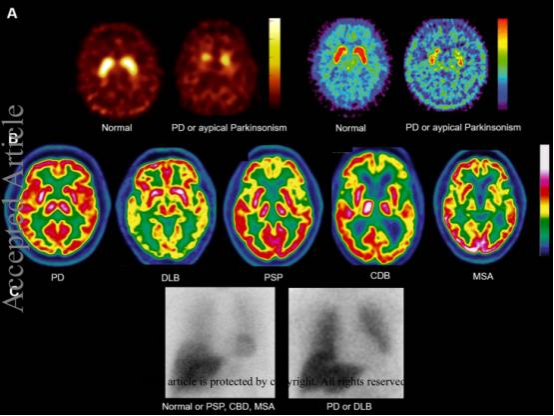

张建军的检查报告显示惊人细节:其梨状皮层葡萄糖代谢率仅为同龄人41%,而运动皮层尚且保持83%活性,印证嗅觉系统是神经退变的最早哨站。

上海瑞金医院案例库中,某49岁金融高管因持续无法辨别普洱茶香,经PET-CT发现壳核多巴胺转运体密度仅剩正常值58%,确诊时尚未出现任何震颤。